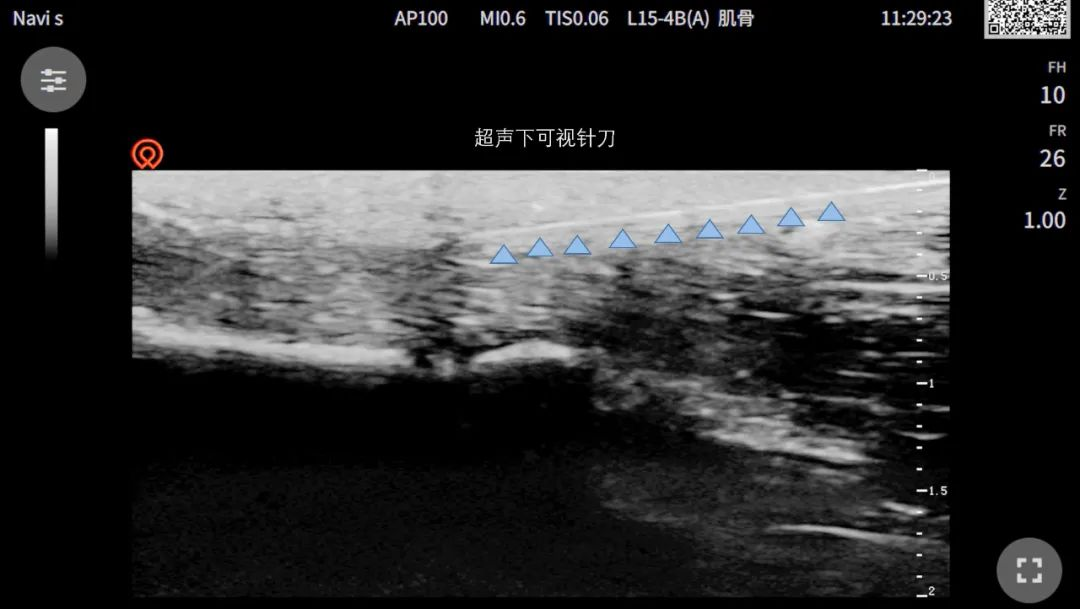

治疗扳机指“新武器”-可视化下针刀治疗

疼痛科门诊病例:患者右手拇指伸直受限,掌指关节疼痛数月,经超声引导下针刀松解治疗,效果立竿见影,症状明显改善。

小针刀具有无痛、无瘢痕、疗效高、操作简单等优势,但因传统小针刀的实施多在盲视下操作,受操作者经验影响因素大,针刀治疗的可视化成为临床研究的方向。超声技术如同医生的第三只眼,能够实时显示病变部位的结构,引导小针刀精准到达病变腱鞘处,有效避开重要神经、血管,极大降低了治疗并发症的风险。